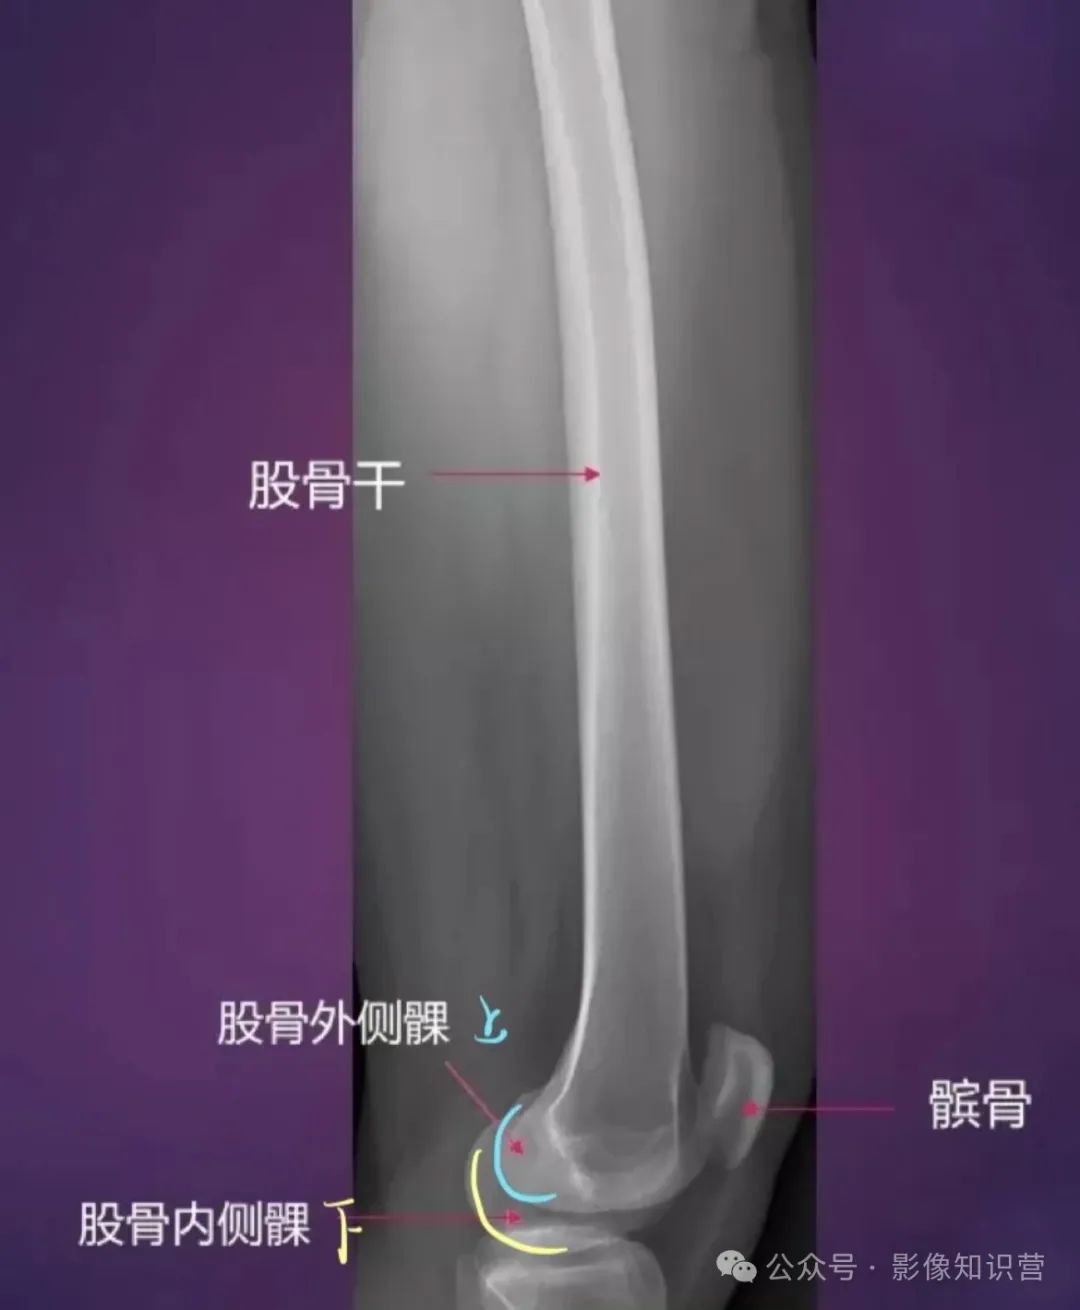

股骨:是人体最长最结实的长骨。股骨头呈球形,与髋臼构成髋关节。股骨颈与股骨干之间形成颈干角。股骨体后方有粗线,是肌肉附着处。股骨下端有内侧髁和外侧髁,与胫骨和髌骨相关节。

解剖标志:股骨头、股骨颈、大转子、小转子、股骨干、股骨髁(内、外侧髁)。

影像要点:股骨颈骨折分型(头下型、经颈型、基底型)

膝关节骨骼组成:股骨远端、胫骨近端、髌骨。

影像特征:X线侧位:观察髌骨位置及关节间隙(正常约3-5mm)。MRI可评估半月板(内“C”形、外“O”形)、交叉韧带及软骨损伤。